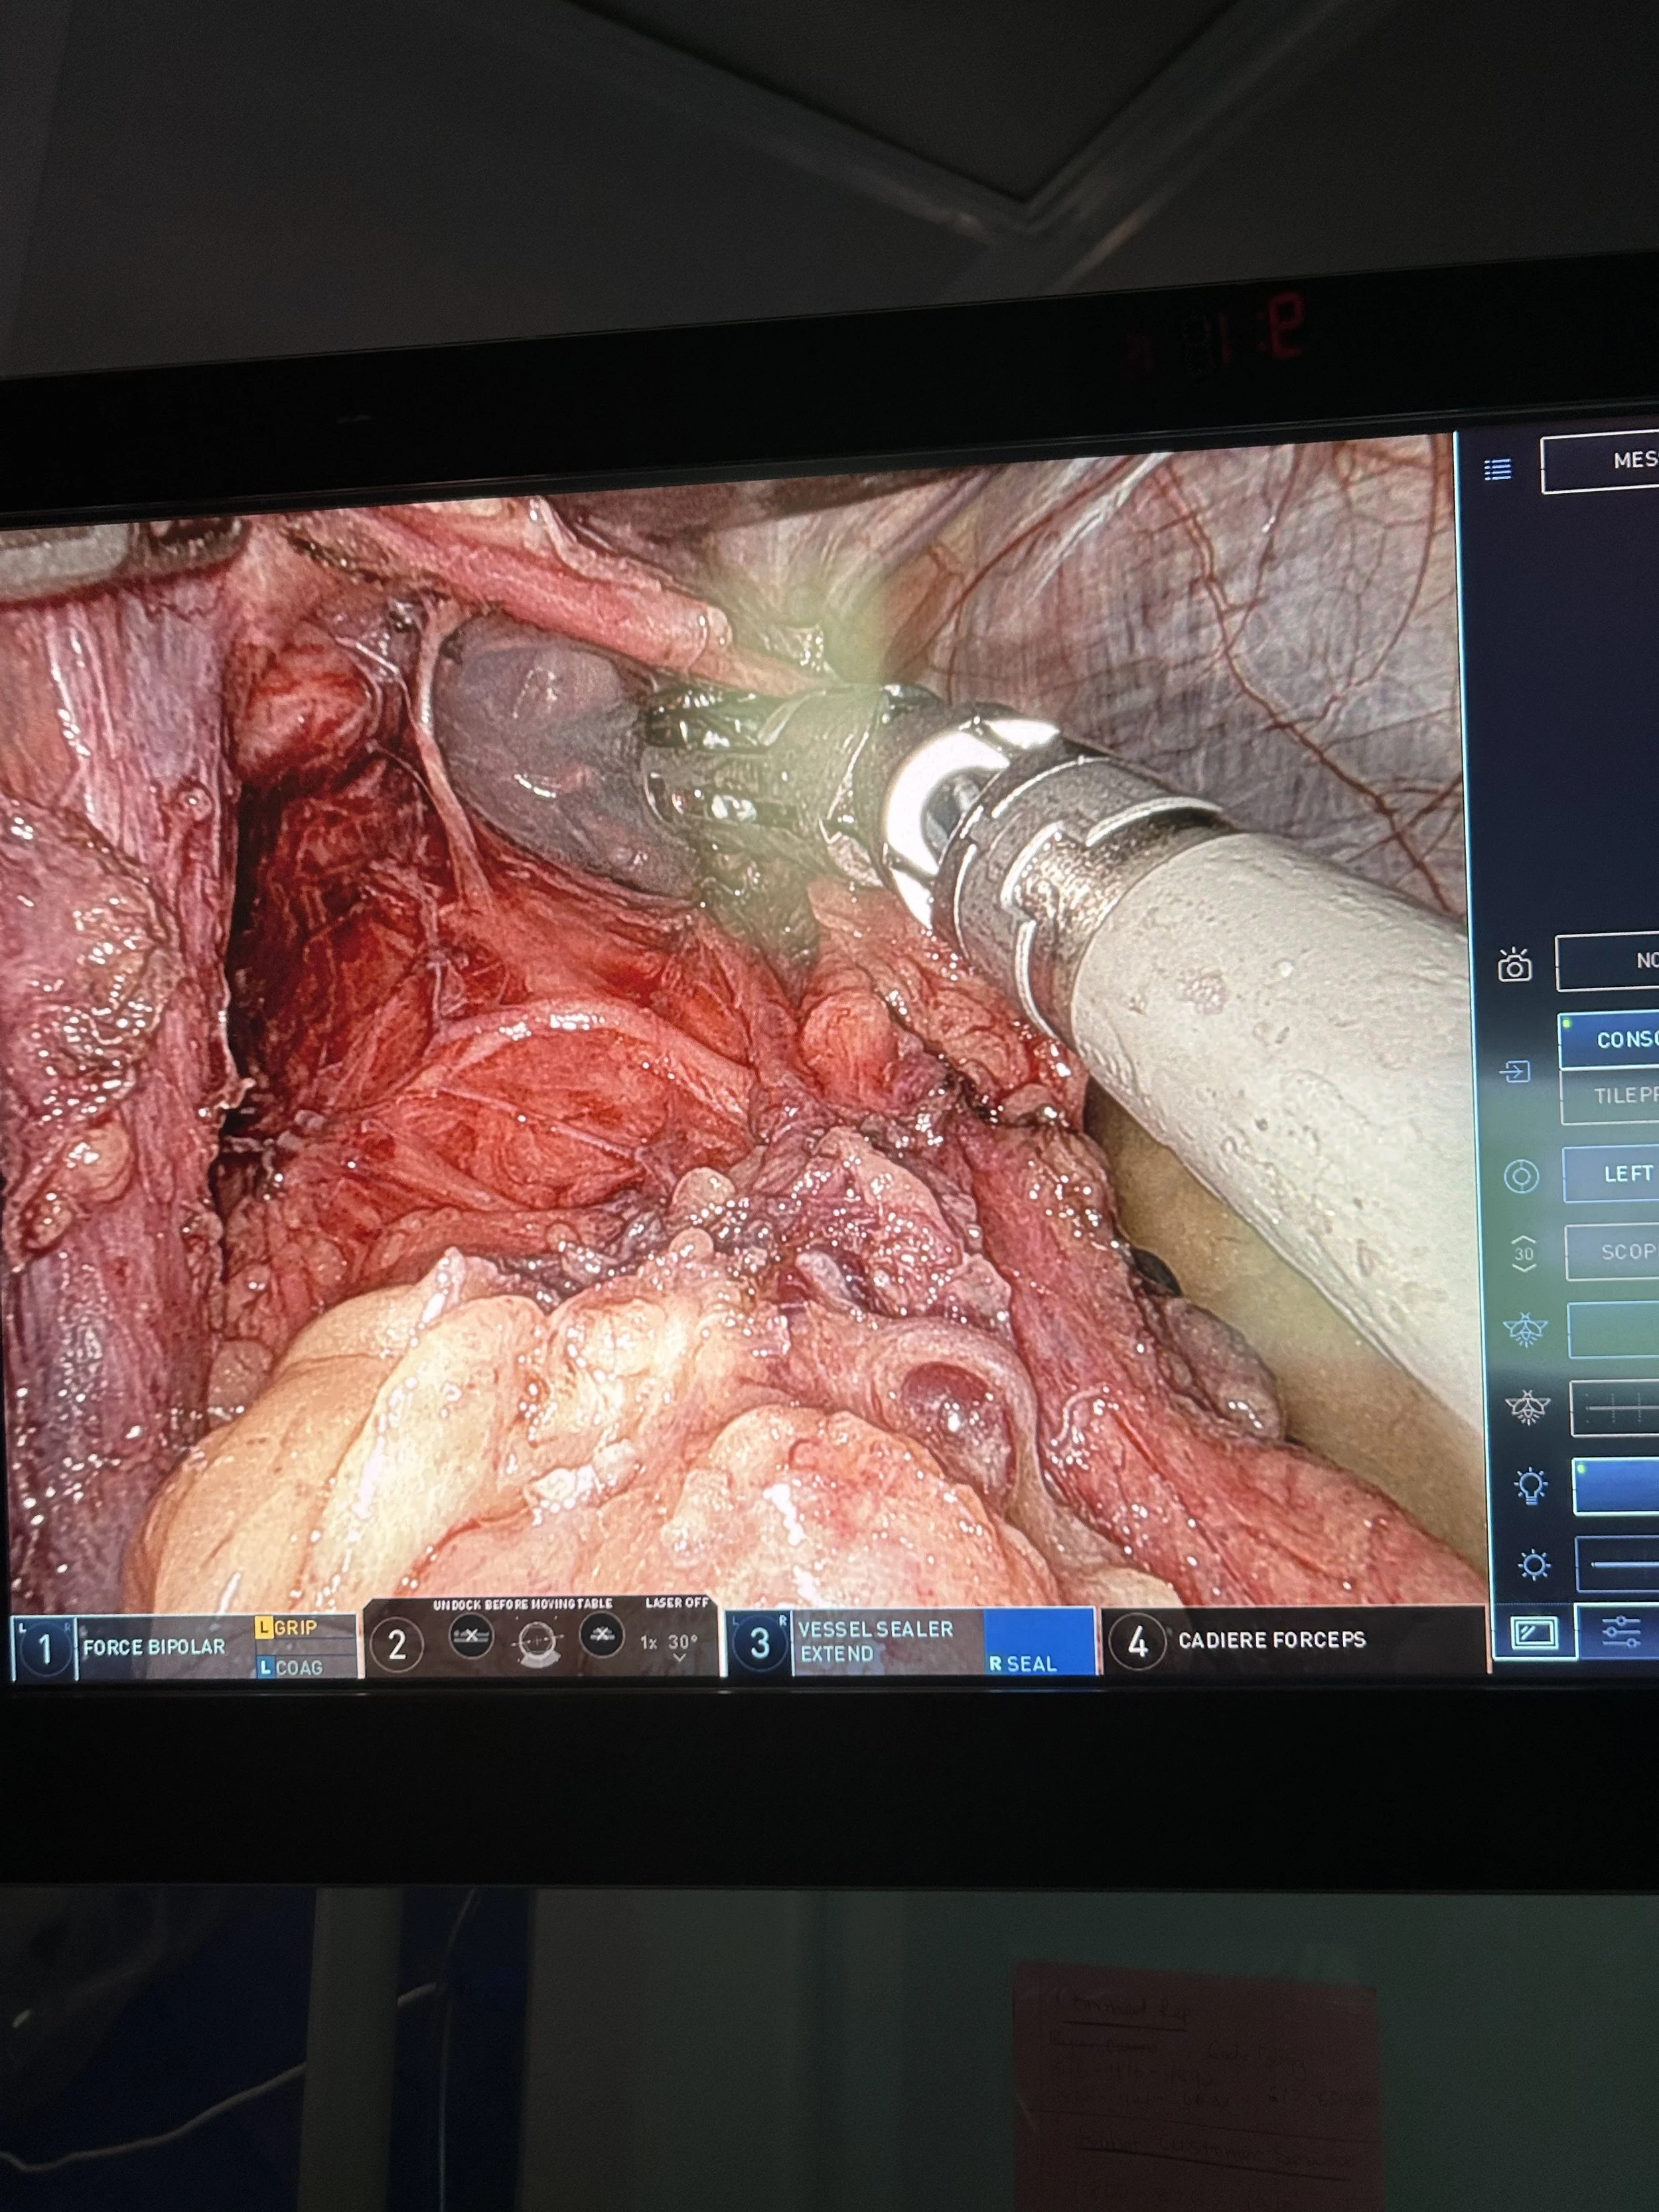

View of the anterior vagus nerve during mediastinal dissection of a paraesophageal hernia, enabled by liver retraction accomplished by our hybrid snake retractor + Nathanson bed post.